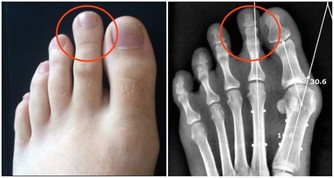

研究證明,阿爾茨海默病患者大部分是散發,但是部分有家庭聚集的傾向。目前已經明確與阿爾茨海默病相關的基因有四對,分別為APP、PS1、PS2、APOE4基因。